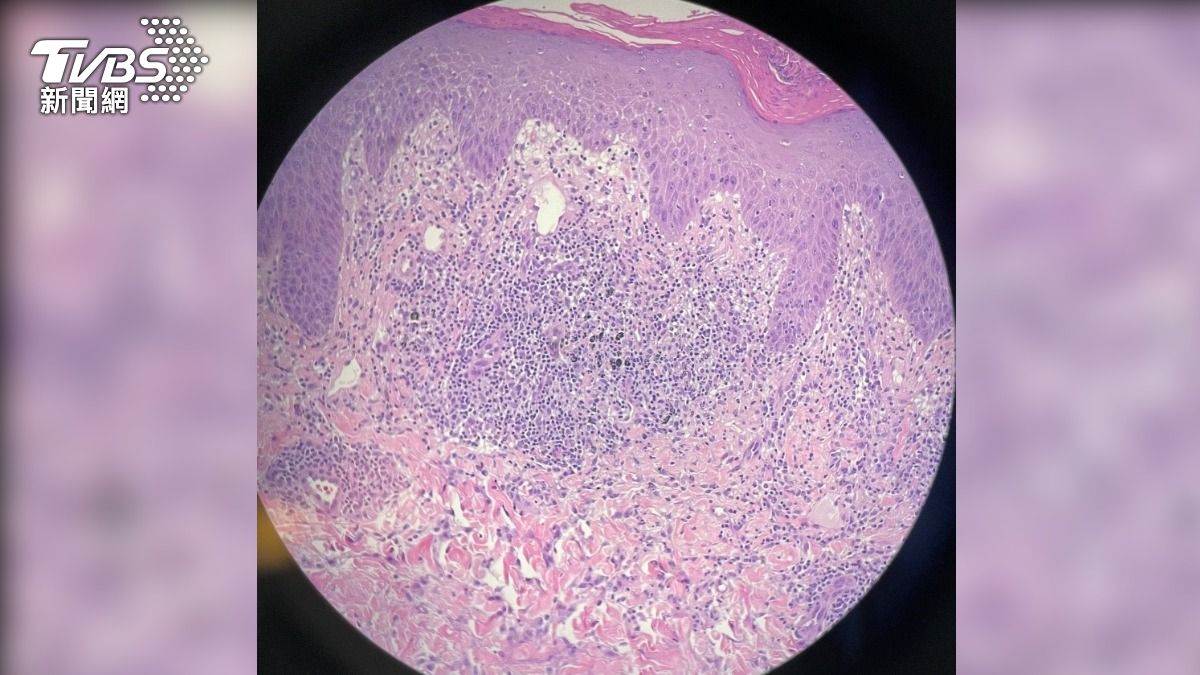

安南醫院皮膚科主任羅子焜表示,經病理切片檢查發現,男子的丘疹起因于皮膚對黑色顏料過敏,引起刺青肉芽腫反應所致。後續經口服藥物1個月,外觀已恢復正常,不適癥狀也得到緩解。